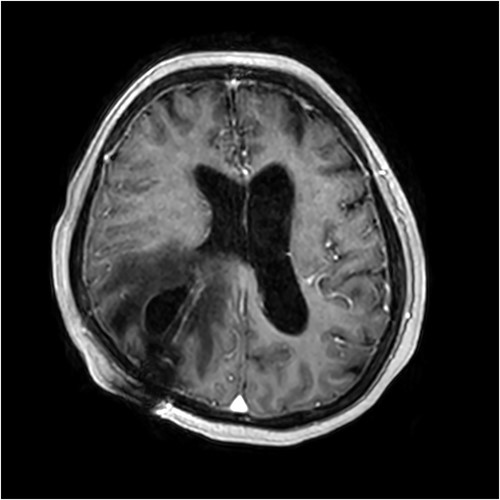

A 67 year-old woman was admitted to our service from the neurosurgical department for rehabilitation after a spontaneous left basal ganglia haemorrhage and diffuse intraventricular haemorrhage with hydrocephalus. She had been initially found unresponsive at home with coffee ground vomitus and incontinence of urine. An urgent computed tomography (CT) scan of the brain showed a large intracranial haemorrhage with intraventricular bleeding and hydrocephalus (Fig. 1). Her acute admission involved an extraventricular drain inserted by the neurosurgery service. A repeat CT brain performed 10 days later showed stable multicompartmental haemorrhage, and the extraventricular drain was removed. A ventriculoperitoneal shunt was inserted on Day 27 for ongoing management of the hydrocephalus. A digital subtraction angiogram showed no underlying aneurysm or arteriovenous shunt.

Initial CT revealing acute left-sided intraparenchymal haemorrhage with intraventricular extension and mass effect.